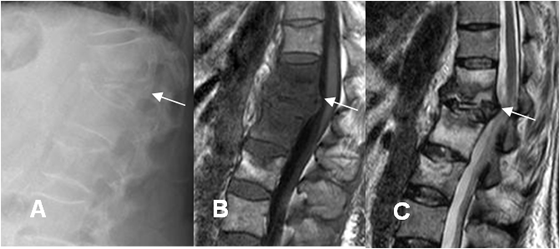

Fig 147 C. Espondilodisquitis TBC.

A: Rx lateral. Gran pérdida de altura en el cuerpo de L1.

B: RM sagital en T1 y B: RM sagital en T2. Adicional al aplastamiento de L1, (Flecha delgada), se encuentran cambios inflamatorios en D12, L2 y L3. el compromiso de varios cuerpos hace sospechar etiología TBC, que se confirmó.